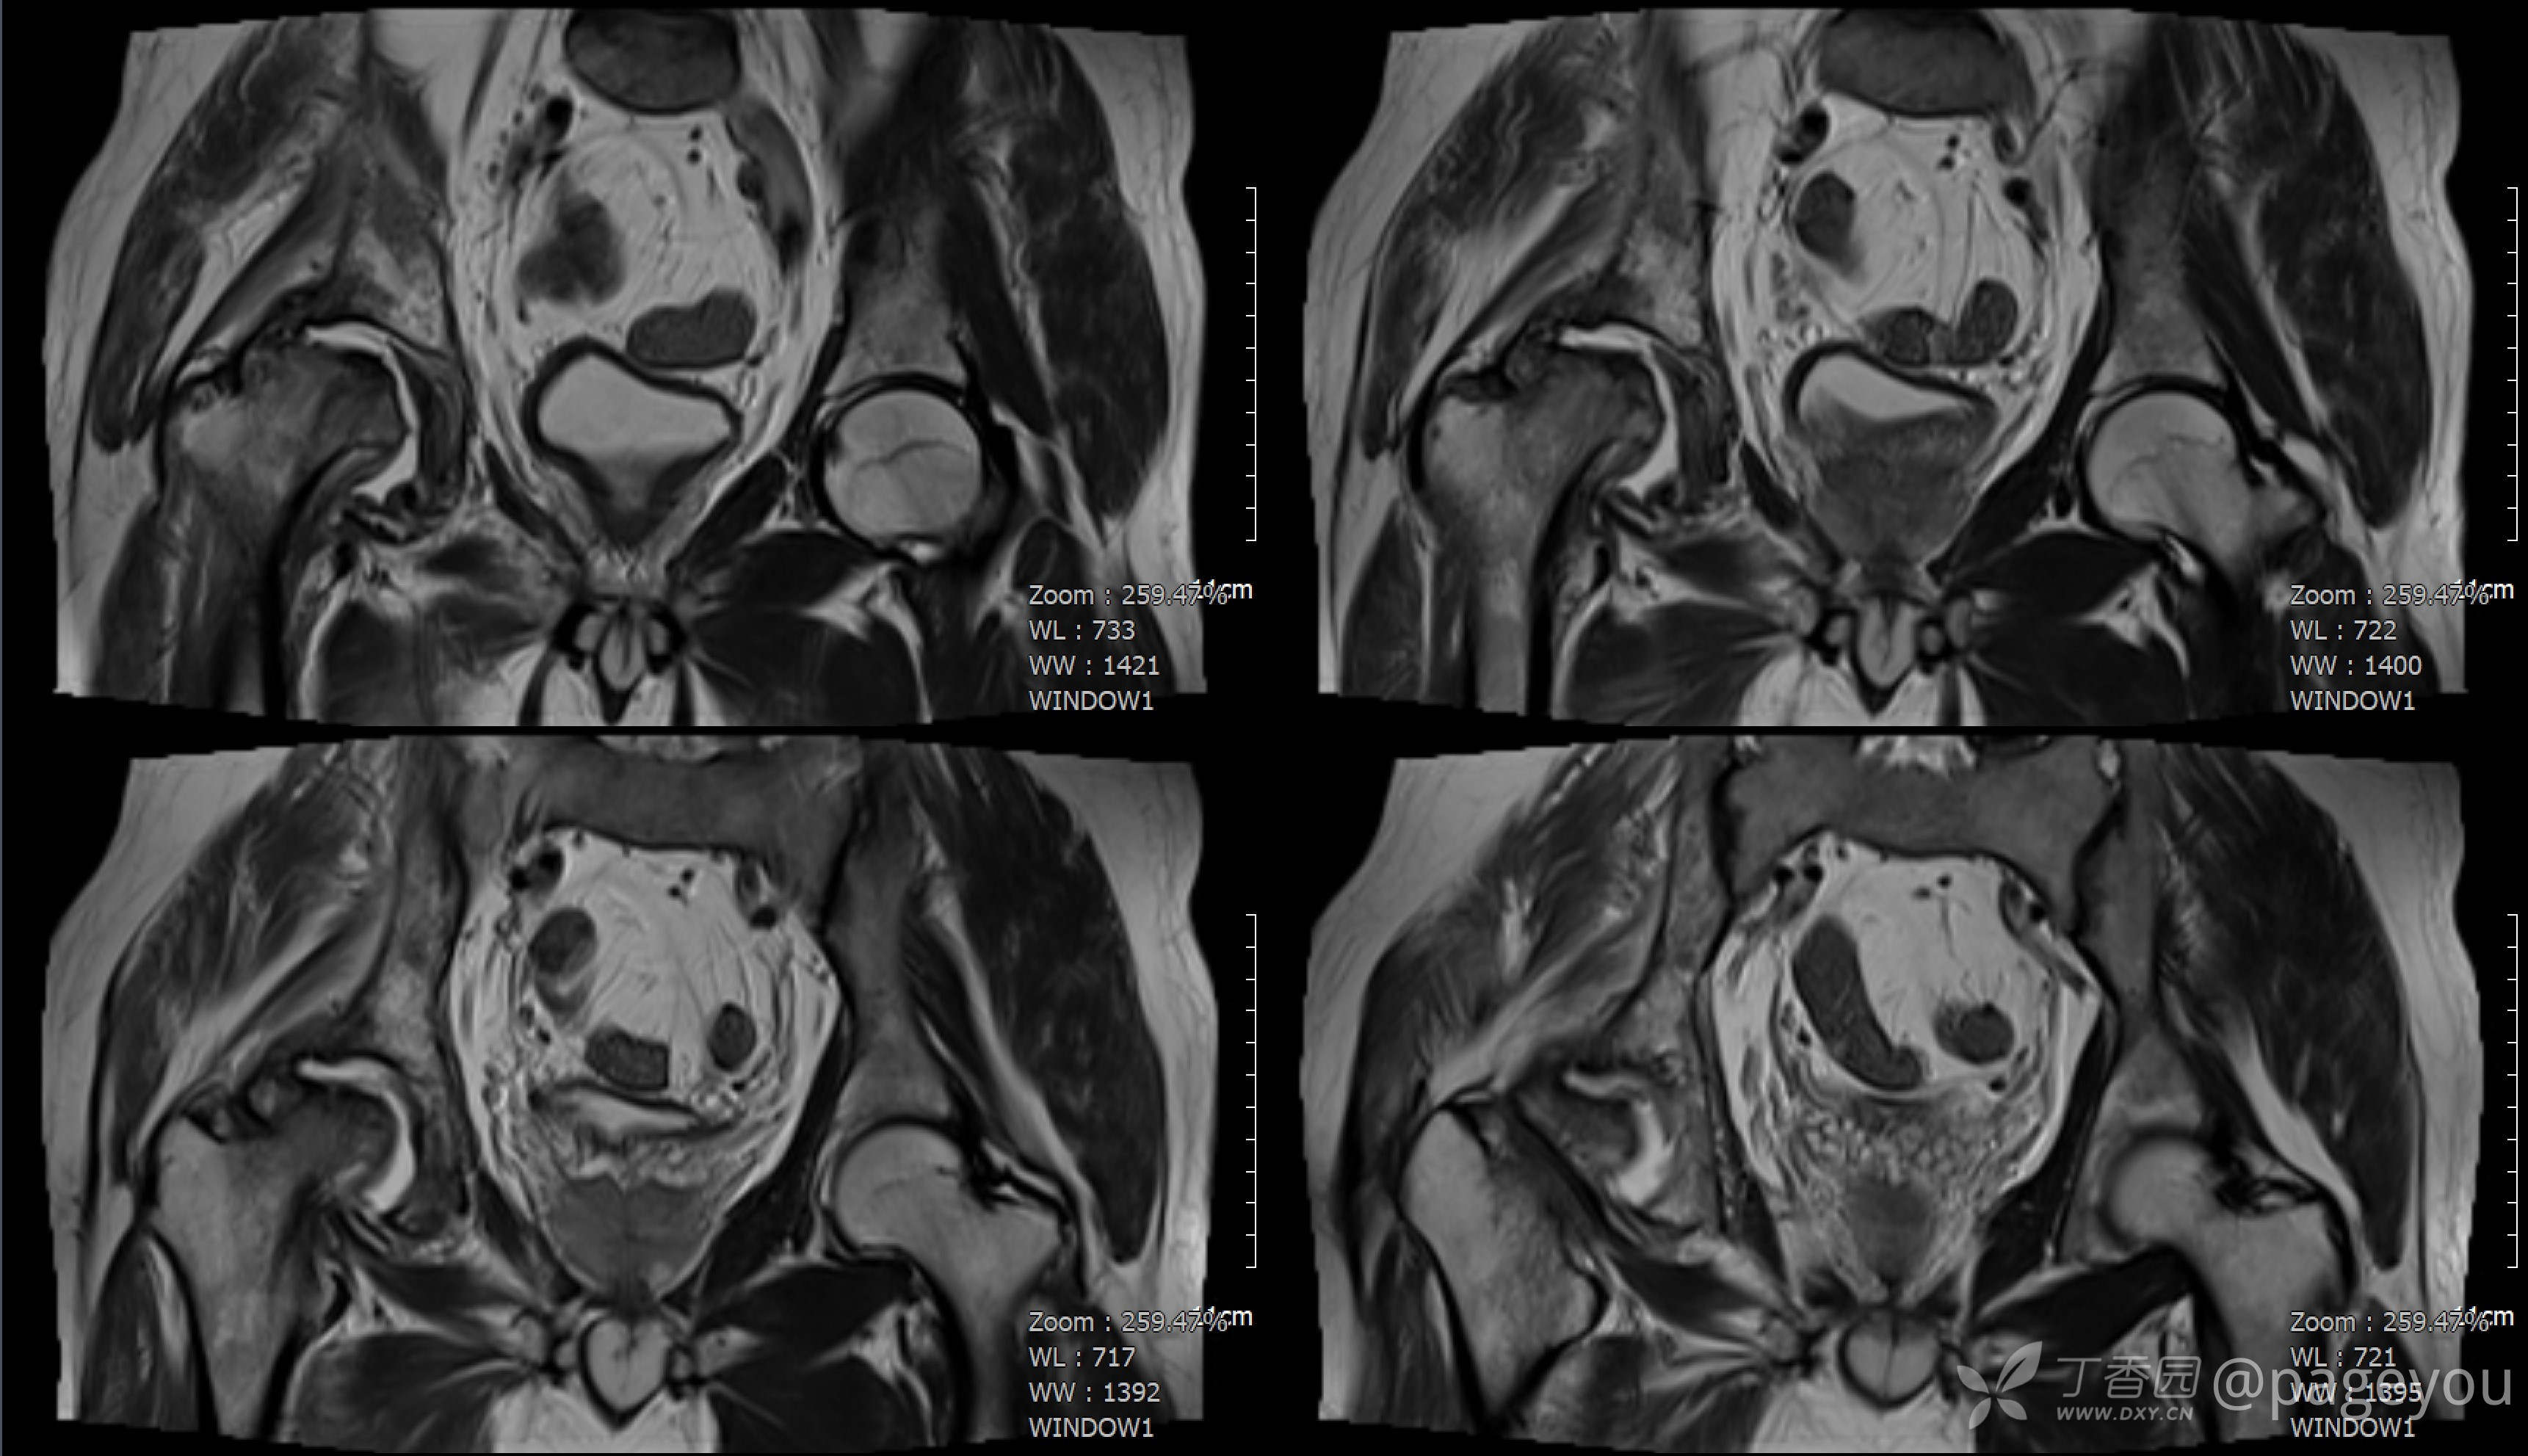

查骨盆MRI: